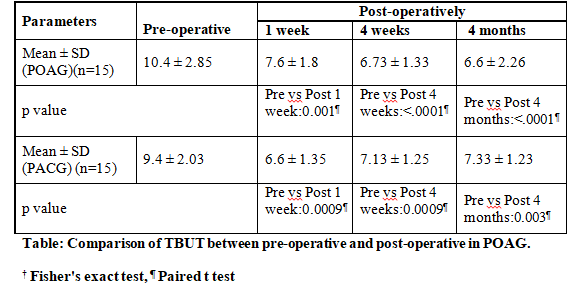

TBUT assessment is shown in Table:

Comparison between POAG & PACG was not statistically significant.

groups and remained at 4 weeks despite removal of releasable sutures. Tear film disruption was noted. There were improved TBUT readings over time, but residual TBUT reduction remained till 4 months. Intergroup difference at all

times was NS in both groups.